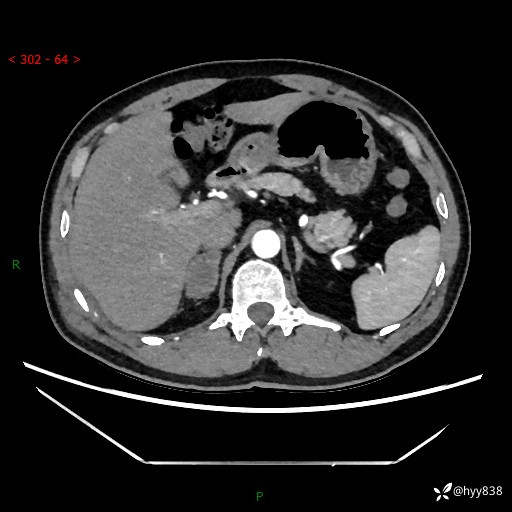

现病史:患者9月4日摔伤在深圳市宝安区中心医院行CT检查提示右侧肾上腺区结节(38*27mm),复查B超提示右侧肾上腺区可见一61*24mm异常低回声团,建议进一步检查。进一步完善增强CT后提示:右侧肾上腺区肿块及周围渗出改变,大致同前,考虑肾上腺腺瘤,不除外瘤内出血可能,否认阵发性头晕、头痛、出汗、乏力等不适,门诊以“ 右侧肾上腺肿瘤”收入住院。 起病来,患者精神、食欲、睡眠可,大便通畅,小便如上述,体力体重无明显改变。

肾上腺CT平扫

增强(动脉期+静脉期)